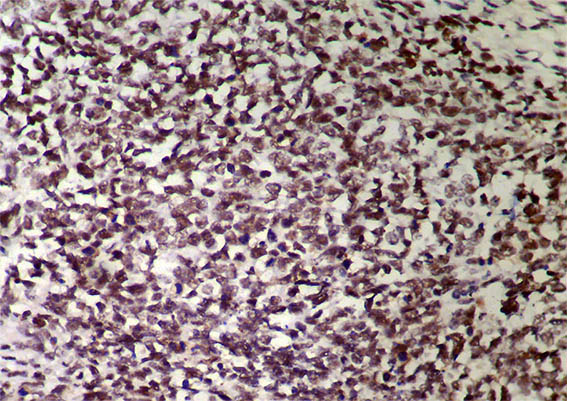

Figure 11. Immunohistochemistry for WT1 completely negative, X400.

Figure 12. Immunohistochemistry for Cyclin D1: diffuse nuclear positivity, X400.

Myogenin, CD99, CD45, S100, chromogranin, synaptophysin, cytokeratins: Negative. INI1: diffuse nuclear positivity.